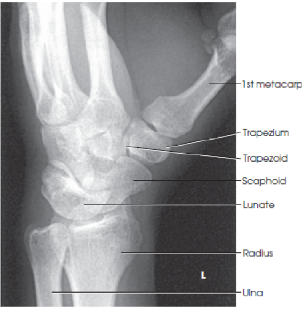

What are the structures shown in a lateral wrist image

distal radius and ulna, carpals, and proximal half of metacarpals